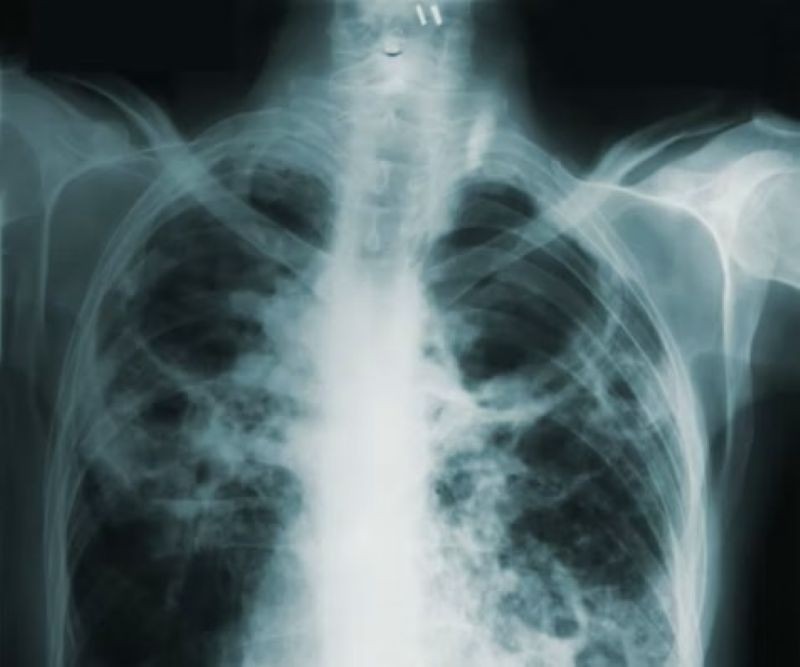

End of Tuberculosis? New tools spark hope of a global breakthrough